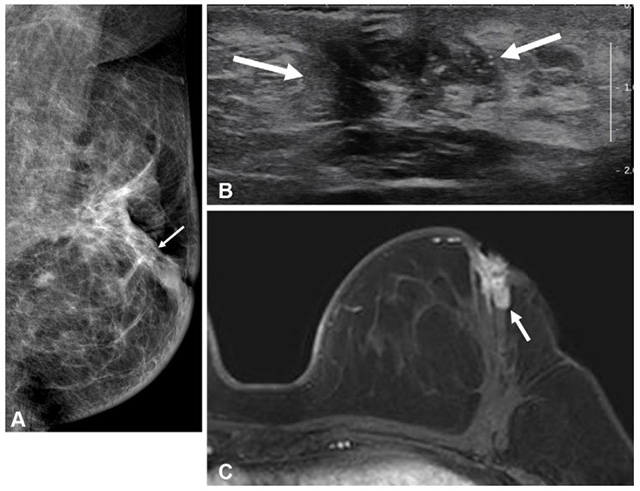

• 수술 전 MRI 검사를 시행하지 않은 50세 이하 유방암 환자의 수술 2년 후 영상. (A) 유방촬영술, (B) 초음파, (C) MRI. 동측 유방 내 재발 병변(화살표)이 관찰된다. /이미지 제공=서울대병원

▲ 수술 전 MRI 검사를 시행하지 않은 50세 이하 유방암 환자의 수술 2년 후 영상. (A) 유방촬영술, (B) 초음파, (C) MRI. 동측 유방 내 재발 병변(화살표)이 관찰된다. /이미지 제공=서울대병원